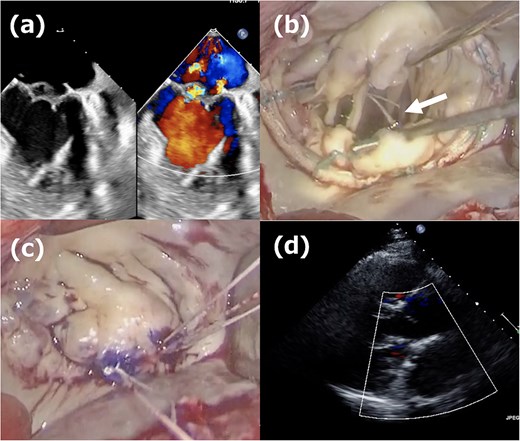

Second operation images. (a) Moderate mitral regurgitation caused by partial prolapse of the A2 segment, observed 3 weeks after the initial operation. (b) Intraoperative image showing the rupture of the ePTFE loop at the fixation site onto the leaflet during reoperation. (c) Three 20-mm long CV4 loops were attached to the posterior papillary muscle, and those loops were fixed to the A2 segment with CV4. (d) One week postoperative echocardiogram showing no residual mitral regurgitation after reoperation.

The second operation was performed 1 month after the initial operation. The approach employed was identical to that of the first operation; right-sided minithoracotomy was performed via the fourth intercostal space. Although access to the heart was more challenging due to adhesions, the operation proceeded in the usual manner, including femoral cannulations, aortic cross-clamping with antegrade cardioplegia, and right-sided left atriotomy. The most medial loop was ruptured at the fixation site onto the leaflet (Fig. 2b). The previously implanted annuloplasty band was removed, and three 20-mm CV4 loops were attached to the posterior papillary muscle and fixed to the A2 segment with CV4 (Fig. 2c). Thereafter, a new 34-mm annuloplasty ring (Physio II, Edwards Lifesciences, CA) was then implanted. Postoperative TTE confirmed no residual MR (Fig. 2d), and the patient remained free of recurrence at 1-year follow-up.